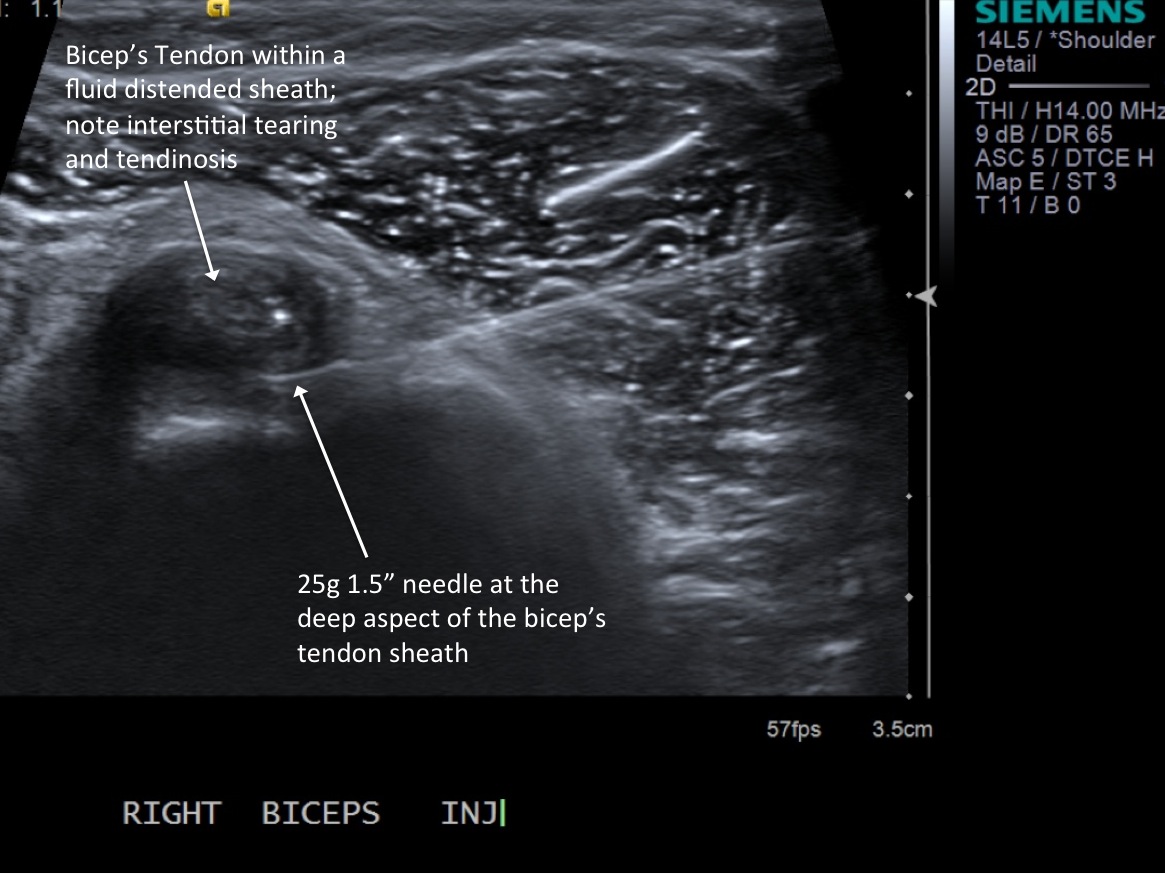

Procedure Instructions:

10. With ultrasound guidance, advance the 25g needle into the sheath surrounding the tendon.

• descriptiondescription

11. Test inject to see if easy flow with 1% lidocaine. If no resistance and see distention of the tendon sheath, exchange for 3cc syringe with injectable steroid and ropivacaine.